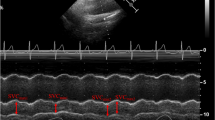

Forty-five consecutive patients undergoing scheduled open major vascular surgeries, including open abdominal aortic aneurysm or Leriche syndrome repair procedures, from September 2013 to November 2016 were recruited for the study. We excluded patients who met any of the following criteria: age younger than 18 years, with suspected pregnancy, non-sinus cardiac rhythm, weight > 120 kg or < 60 kg, left ventricular ejection fraction ≤ 30%, right ventricular dysfunction (right ventricular ejection fraction ≤ 30% on preoperative TTE), significant pulmonary hypertension [23] (mean arterial pulmonary pressure ≥ 35 mmHg on preoperative TTE), preoperative vasodilator, vasoconstrictor, or inotrope treatments, renal failure requiring haemo- or peritoneal dialysis, haemoglobin < 8 g dl−1, significant aortic regurgitation [24] and a history of oesophageal or gastrointestinal disease precluding TEE. After premedication with intramuscular morphine at a dose of 0.1 mg kg−1, all patients were transferred to the operating room and standard non-invasive monitoring was initiated. Two peripheral venous lines and a radial artery catheter were inserted. General anaesthesia was induced with fentanyl 7 mcg kg−1, midazolam 0.1 mg kg−1 or Propofol 1.5 mg kg−1, and atracurium 0.6 mg kg−1 and maintained with sevoflurane (for minimum alveolar concentration 0.8–1.2 and a bispectral index 40–60), fentanyl, and atracurium as needed for ventilator-adaptation maintenance. After endotracheal intubation, controlled mechanical ventilation was instituted in all patients according to the following parameters: FIO2 0.6, tidal volume 8 ml kg−1, frequency of 12 cycles min.−1, peak inspiratory pressure < 25 cm H2O, I:E ratio 1:2, and a positive end-expiratory pressure of 5 cm H2O to maintain the end tidal CO2 at 30–35 mmHg. These mechanical ventilation parameters were unchanged throughout the surgery. The arterial line was connected to a FloTrac sensor (Edwards Lifesciences, Irvine, CA, USA) and a Vigileo monitor (Edwards Lifesciences, Irvine, CA, USA; software version 4.02). Eventually a three-way central venous catheter was inserted into an internal jugular vein, and a urinary catheter and an hTEE probe (ClariTEE™, ImaCor Inc., Garden City, NY, USA) coupled to a ZURA-EVO 1™ console (ImaCor Inc., Garden City, NY, USA) were inserted. The FloTrac and venous transducers were zeroed to the level of the left atrium and the Vigileo monitor was set to measure the cardiac index (CI) and SVV at 10-s intervals on the basis of a proprietary algorithm described in detail elsewhere [25]. The hTEE probe was fixed in the ME-AA-SAX view. Once the patient was monitored and stable, maintenance fluid, either 5% dextrose or Ringer’s lactate solution (at the discretion of the treating physician) at 1 ml kg h−1 was administered throughout the intraoperative period. Hypothermia was minimized using forced-air warming blankets. Intraoperatively, standardized volume loading tests (VLT) with 500 ml of a gelatine solution (Gelofusine 4 g/100 ml, B. Braun, Germany) were administered over 10 min any time one or any combination of the following circumstances were present: systolic arterial pressure (SAP) decreased ≥ 40 mmHg from baseline, SAP < 90 mmHg, mean arterial pressure (MAP) decreased ˃20% from baseline, MAP < 60 mmHg, tachycardia > 100 beats min−1, hyperlactatemia > 2 mmol l−1, urine output < 0.5 ml kg−1 h−1 for 60 min, or estimated blood loss ≥ 500 ml. Boluses of ephedrine or norepinephrine were given whenever the treating physician deemed necessary but all the VLTs preceded by those boluses were excluded from the study [26]. The following haemodynamic parameters were studied before and after each VLT: heart rate (HR), SAP, MAP, CI, CVP, SVV, and hSVC-CI. Aside from the above-described VLTs, any other fluids, red blood cells (transfused to maintain the haemoglobin > 8 g dl−1), or blood products administered between the VLTs were not counted in the VLTs. One senior anaesthesiologist blinded to the SVV and hSVC-CI measurements managed the intraoperative status of the patients (standardized VLT administrations included). Another anaesthesiologist collected the invasive haemodynamic data (HR, SAP, MAP, CI, CVP, and SVV) during 12-s periods before and after the VLTs were administered. A third blinded anaesthesiologist was dedicated to maintaining the best SVC view and recording two consecutive cine-loops of the ME-AA-SAX views (each for 6 s) when the first anaesthesiologist announced that either a VLT condition was present or the end of each VLT. All invasive haemodynamic data were also recorded in our patient data management system (HIM-GmbH, Bad Homburg, Germany) for review and analysis. The best SVC view was defined as the first SVC short axis view visualised during the gradual withdrawal of the monoplane probe from the four chambers view. The hSVC-CI was calculated offline using the formula:

The maximum and minimum areas were measured offline by tracing the SVC borders. The average hSVC-CI from two consecutive cine-loops was used for statistical purposes. CI increases induced by volume expansion were used to classify each VLT as ‘positive’ (+) (≥ 11% increase in CI) or ‘negative’ (−) (< 11% increase in CI) for further analysis.

Thirty-one patients were men and nine were women, with an overall mean age of 63 ± 9 years (men: 65 ± 9, women: 63 ± 11). A total of 289 VLTs were administered but twenty-three VLTs preceded by vasopressor administration, were excluded. For the 266 remaining VLTs, the median number of VLTs per patient was 7 (range 3–8). The mean estimated blood loss was 1225 ml ± 305 ml. No patient received inotropic therapy during the study. All patients survived and no complication linked to hTEE usage has been highlighted. Table 1 summarizes the results of the haemodynamic measurements at baseline and after the VLTs. Of 266 VLTs studied, 243 (91%) were positive (≥ 11% increase in CI) and only 23 (9%) were negative (< 11% increase in CI) (Fig. 1). Among the 266 VLTs studied and the 243 +VLTs, we found a significant decrease from baseline to post VLT administration in both hSVC-CI and SVV. This was accompanied by a significant increase in CVP and CI (Table 1). Among the 23 negative VLTs the hSVC-CI, SVV, CVP and CI values did not change (Table 1). A comparison of variables measured at baseline between +VLTs and −VLTs showed significantly higher hSVC-CI (0.44 [0.39 to 0.51] vs. 0.35 [0.32 to 0.36] % P < 0.0001) and SVV (18.0 [16.0 to 21.0] vs. 13.0 [12.0 to 14.0] %; P < 0.0001) values and significantly lower CI (2.0 [1.8 to 2.2] vs. 2.5 [2.1 to 2.9] l min −1 m−2; P < 0.0001) values in +VLTs than in –VLTs (Table 1. Also, CVP values (10.0 [7.0 to 13.0] vs. 11.0 [6.0 to 14.0] mm Hg; P = 0.63) did not show any statistically significant difference between the +VLTs and –VLT groups (Table 1). Discrimination between +VLTs and −VLTs according to haemodynamic parameters was then evaluated by constructing ROC curves (Fig. 2). In the ROC curve analysis, both hSVC-CI and SVV showed good predictivity, with AUCs values of 0.92 (95% CI 0.88 to 0.95; P < 0.001) and 0.89 (95% CI 0.85 to 0.93; P < 0.001), respectively. No significant difference was found between the two AUCs (P = 0.56). The AUC for CVP (0.53, 95% CI 0.46 to 0.59; P = 0.69) was significantly lower than that for hSVC-CI and SVV, thus demonstrating poor predictivity for this parameter. The AUC for CVP was not significantly different from 0.5. Based on the Youden test, a baseline hSVC-CI cutoff value > 37% predicted fluid responsiveness with a sensitivity of 90% (95% CI: 86 to 94) and specificity of 83% (95% CI: 61 to 95). Baseline SVV cutoff values > 15% predicted fluid responsiveness with a sensitivity of 78% (95% CI: 72 to 82) and specificity of 100% (95% CI: 85 to 100).

Our results concerning the hSVC-CI threshold value (37%), sensitivity (90%), and specificity (83%) are closer to those of studies conducted in strictly anaesthetized, sedated, and paralyzed patients [13, 14] (as our patients were) than those of studies conducted in a heterogeneous population [15, 16]. Similar to that in Vieillard-Baron’s report [13], a CI increase ≥ 11% was used to discriminate between +VLTs and –VLTs; however, we calculated hSVC-CI on the basis of SVC variations studied in the short-axis view and not on the basis of variations studied in the long-axis view (Fig. 3). Moreover, we calculated hSVC-CI based on SVC area variations, not diameter variations. We considered that measuring SVC-CI in the short-axis view (ME-AA-SAX) based on its area variations (using either hTEE or conventional TEE) could confer advantages and disadvantages, both anatomical and physiological.